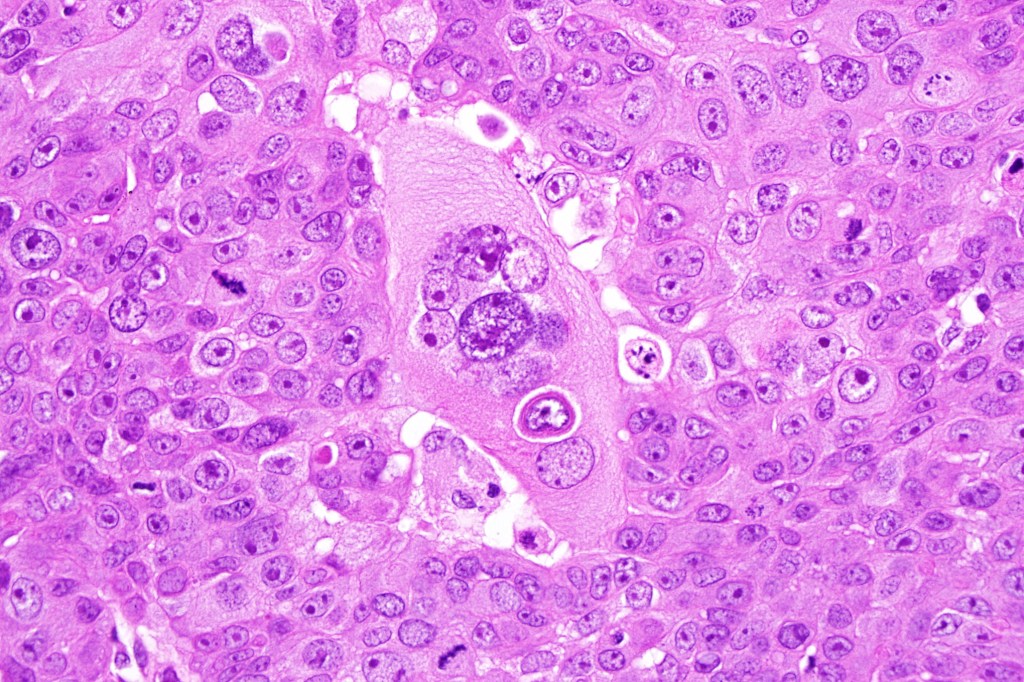

Histological features

•Clear cell change results from cytoplasmic glycogen accumulation

•Exceptionally, this can present with a signet ring-like appearance

If obvious squamous differentiation is not apparent, then metastatic clear cell carcinoma is an important differential diagnosis. Clear cell change may also be seen in a wide range of tumors including basal cell carcinoma, trichilemmal carcinoma, clear cell hidradenocarcinoma, porocarcinoma & melanoma. These are all discussed in respective blogs.